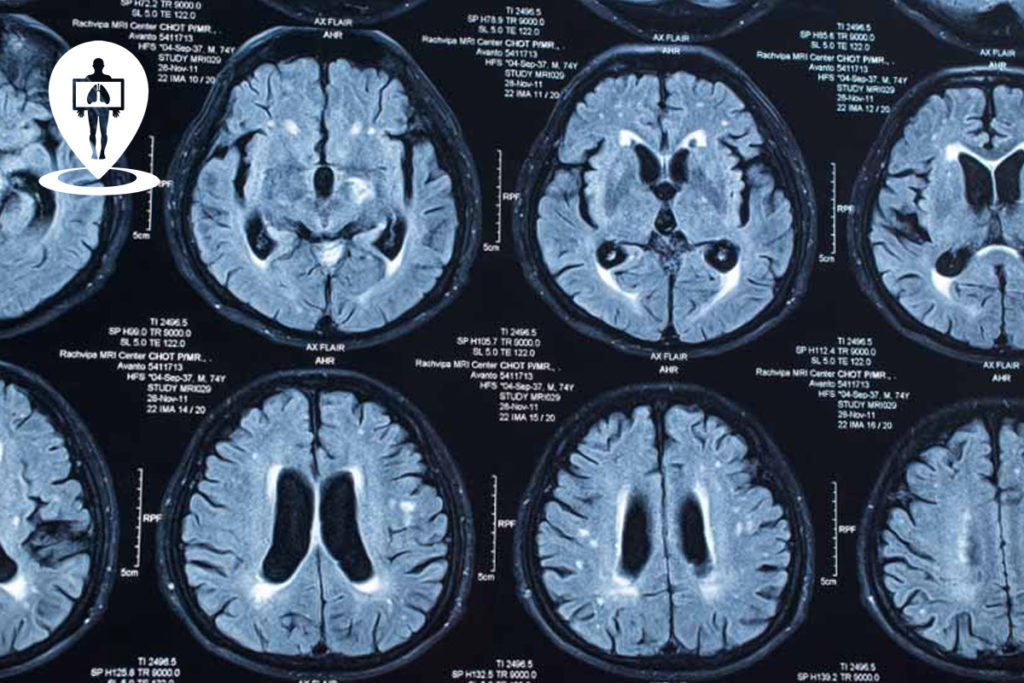

Risonanza cos'è, come funziona e quanto costa mmedical.it

Cos’è la risonanza preparazione e svolgimento.